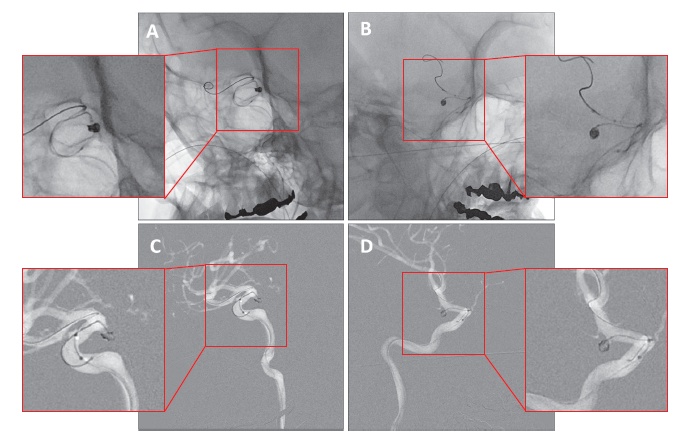

Trinias在脑动脉瘤弹簧圈栓塞术中的性能

更加清晰的图像辅助神经科介入手术轻松自如!